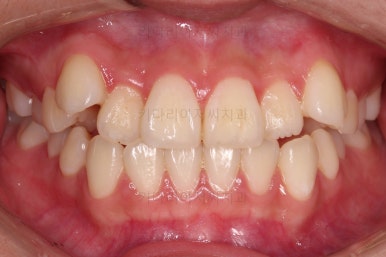

오늘 연산동교정치과 키다리아저씨치과에서 소개해 드릴 환자분은 덧니때문에 교정하고자 하셨던 분입니다.

연산동교정치과 키다리아저씨치과에서 초진 시 얼굴 모습입니다.

다만, 웃을 때 치열이 삐뚤다 보니 활짝 못 웃게 되고 드러나는 치열이 심미적이지 못하네요.

입 안을 보면 밑에 치열이나 다른 부분은 비교적 양호한데 유달리 윗니 송곳니만 위치가 좋지 못하네요.